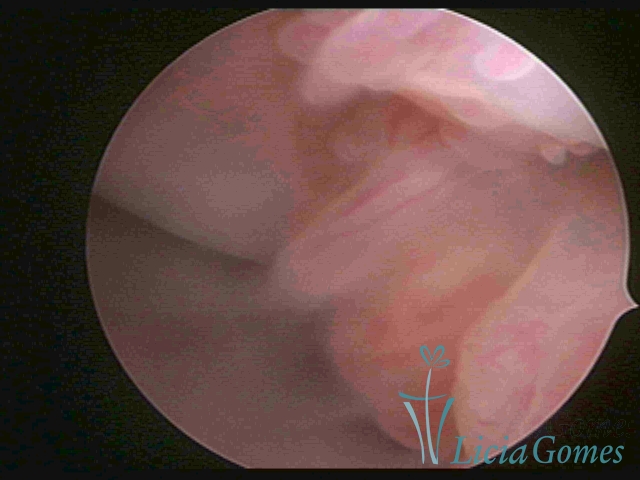

PÓLIPOS ENDOCERVICAIS

São tumores benignos, resultantes da proliferação focal reativa aos processos inflamatórios ou à situações de hiperestrogenismo, e podem ter sésseis (com a base de implantação larga) ou pediculados do epitélio.